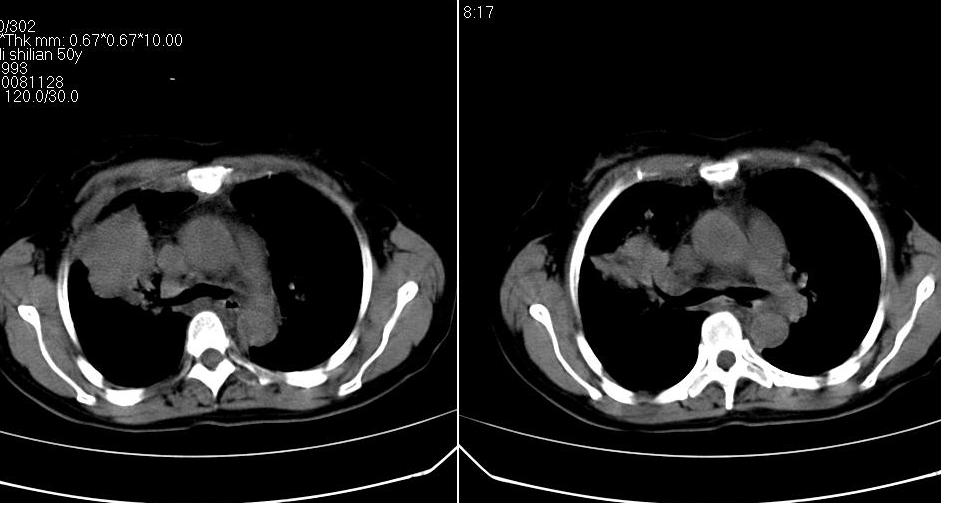

标题: CT16839:胸部CT平扫

女 50岁,在其他医院确诊肺癌.

支持 右肺上叶肺癌并两肺及纵隔转移。

考虑 肺癌伴肺及纵隔转移,心包膜增厚